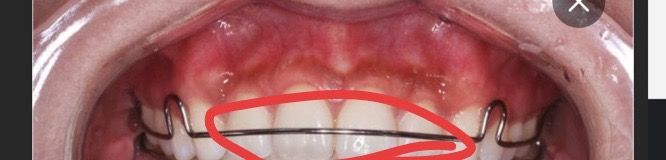

가철식유지장치 철사 톡톡 건들었을때 철사 흔들림

딱딱 소리나게 위아래 맞췄는데 이 표면을 둘러싼 철사를 손으로 위아래 움직이면 움직여져요 원래 이런 건가요…? 답변 부탁드릴게요ㅠㅠ

• 1번 째 사진

네 철사부위는 약간의 움직임은 있을 수 있습니다. 굽어있는 부위가 전반적으로 치아에 닿아있기만 하면 됩니다.

가철식 유지 장치에 설측 철사는 탄성이 있기 때문에 손으로 건조했을 때 움직이는 것이 정상입니다. 하지만 손으로 자주 만지다 보면 유지. 장치가 변형이 될 수 있기 때문에 장착할 때가 아니라면 손으로 만지지 않는 것이 좋습니다.

가철식 유지장치에 보이는 저 철사는 움직일수는 잇지만 너무 많이 움직이면 어딘가에서 문제가 생겻을 가능성도 잇으니 치과에 가셔서 체크를 한번 받아보세요.